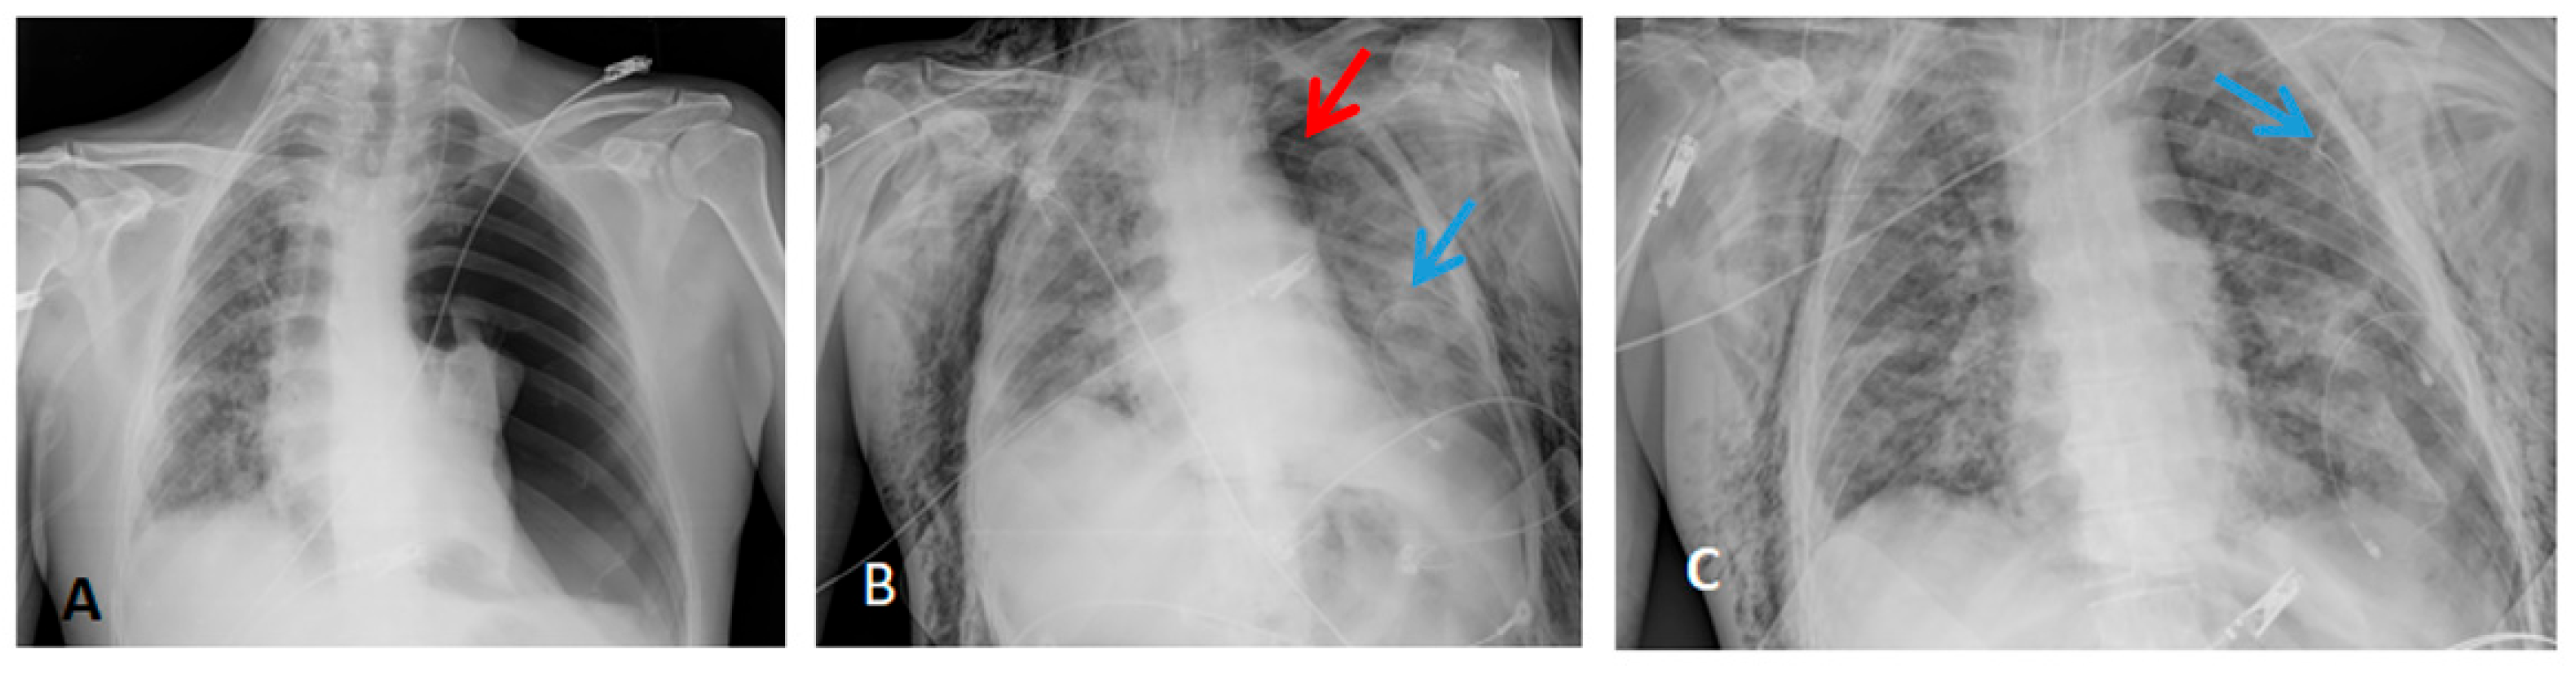

3.3. Radiological Findings